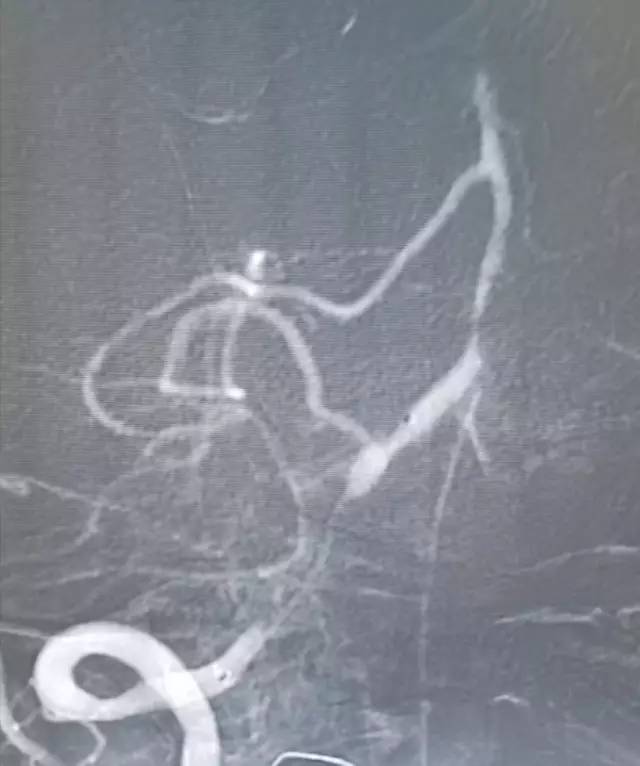

全麻下右股动脉穿刺置入6F动脉鞘,将6F导引导管至右椎动脉V1段,造影:右椎动脉V2段近段及远段狭窄。右椎动脉V4闭塞,右椎动脉V4远段经由脊髓前动脉代偿显影,左椎动脉由对侧椎动脉肌支及脊髓前代偿部分显影(图8)。

图8

路径图下沿导引导管送入Echelon-10微导管携带Pilot 50(0.014” ,190cm)微导丝,通过右侧椎动脉V4闭塞段,撤出微导丝微量造影证实微导管位于闭塞远端正常管腔(图9)。

图9